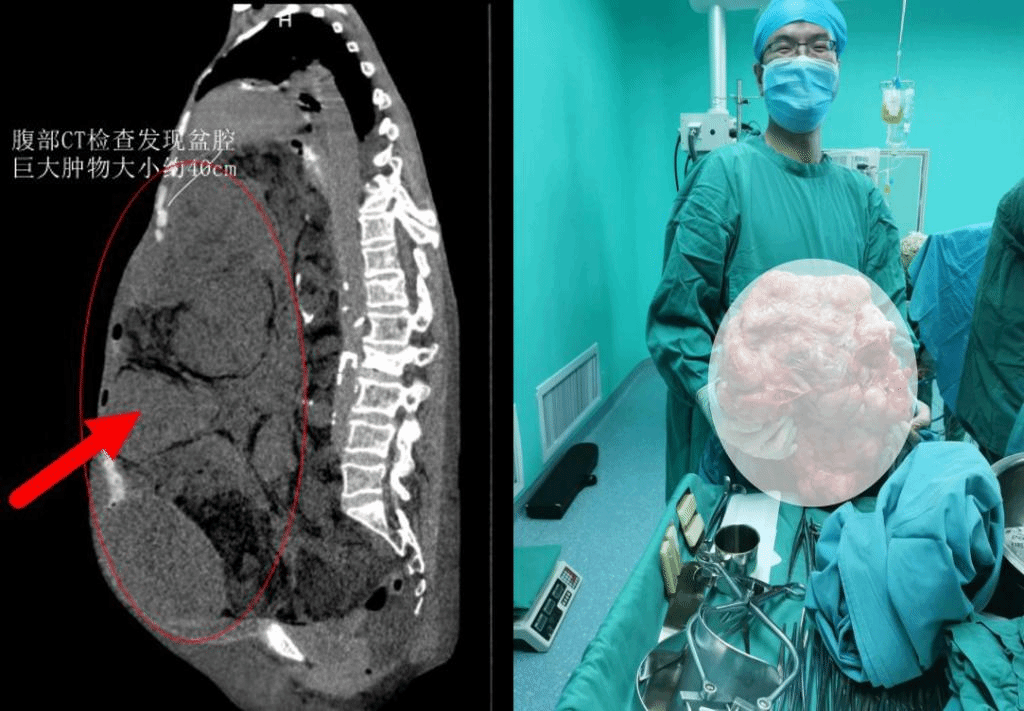

妇瘤二病区诊治。通过腹部CT检查发现盆腔巨大肿物,大小约40cm,患者无法平卧,有心脏病、肺功能下降、下肢静脉血栓、电解质紊乱、贫血等症状。

田小飞主任评估后认为,如此大的腹盆腔包块,在临床中比较罕见,巨大肿瘤让患者的生活质量下降,心理压力增大,甚至会产生严重并发症危及生命。受盆腔巨大肿瘤挤压,患者盆腹腔脏器已经出现移位,失去正常的解剖结构,且手术视野暴露差,肿瘤周边血管丰富,术中易造成临近脏器损伤,随时可能出现大出血、突发的呼吸、循环衰竭等,手术风险极大,手术过程极为复杂。

决定进行多学科协作诊治,该手术由妇瘤病院常务副院长李东红、妇瘤病院二病区主任田小飞、普外科主任马龙安主持,来自手术麻醉科、ICU、护理部的专家与田小飞主任的医护团队进行了充分的术前讨论,制定个性化治疗方案、全周期护理措施,对术中可能出现的各种并发症及风险做好了防范预案。经过积极的术前准备,在手术麻醉科党晓东主任团队的协作下,所有医护人员紧密配合,分工明确,力求把损伤和风险降到最小。术中缓慢抽出淡黄色液体约2000ml后,成功切除大小45cm×30cm,重达40斤的腹盆腔巨大肿瘤。彻底摆脱了腹部重负的马阿姨目前恢复良好。